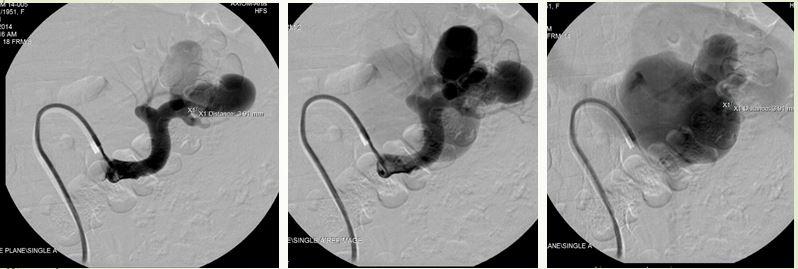

Hình ảnh CT cho thấy túi phình mạch máu khổng lồ trong gan, sát thành bụng

Hình ảnh CT cho thấy một túi phình động mạch gan chung dọa vỡ. Các bác sĩ hội chẩn, nhận định trường hợp này bệnh nhân tuổi cao, vị trí và kích thước túi phình cũng gây khó nếu mổ. BS Cường được mời can thiệp, quyết định gây tắc động mạch gan chung. Sau đó bệnh nhân không bị suy gan hay triệu chứng gì bất thường.

Hình ảnh sau can thiệp, túi phình “biến mất”

Bệnh nhân hết đau bụng, chức năng gan bình thường và tránh được ca phẫu thuật gan ở độ tuổi 75.